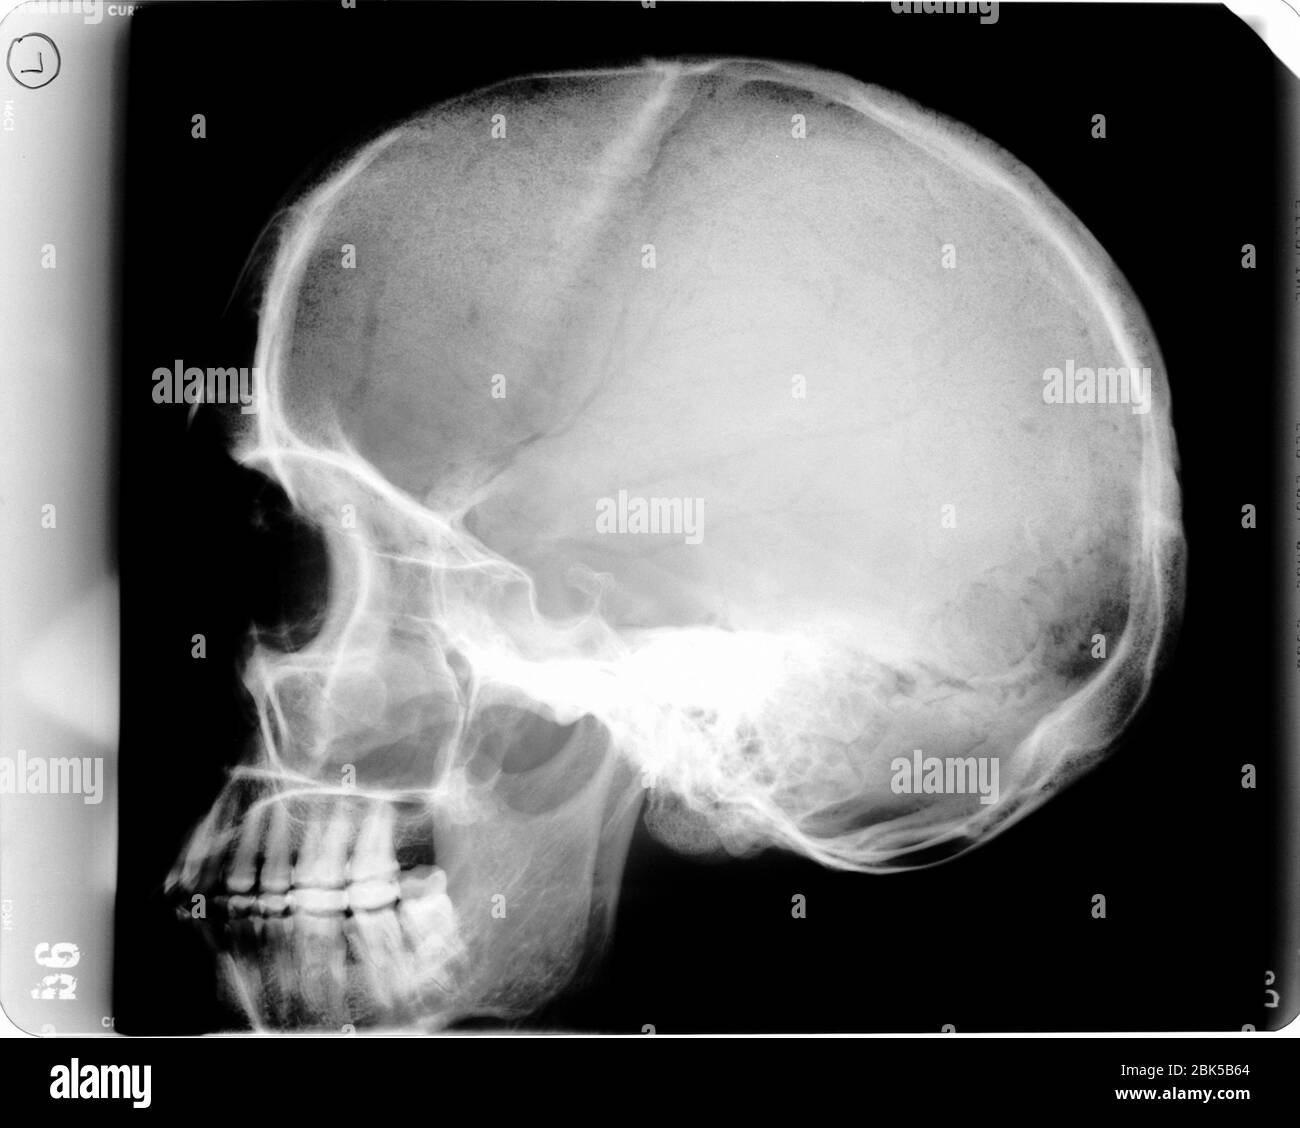

Human skull with light bulb, X-ray. Stock Photohttps://www.alamy.com/image-license-details/?v=1https://www.alamy.com/human-skull-with-light-bulb-x-ray-image356004380.html

Human skull with light bulb, X-ray. Stock Photohttps://www.alamy.com/image-license-details/?v=1https://www.alamy.com/human-skull-with-light-bulb-x-ray-image356004380.htmlRF2BK5B64–Human skull with light bulb, X-ray.

Anatomical X-ray of a Human Skull Showcasing Detailed Structure of Cranium, Facial Bones, and Upper Vertebrae for Educational and Medical Insights Stock Photohttps://www.alamy.com/image-license-details/?v=1https://www.alamy.com/anatomical-x-ray-of-a-human-skull-showcasing-detailed-structure-of-cranium-facial-bones-and-upper-vertebrae-for-educational-and-medical-insights-image684732704.html

Anatomical X-ray of a Human Skull Showcasing Detailed Structure of Cranium, Facial Bones, and Upper Vertebrae for Educational and Medical Insights Stock Photohttps://www.alamy.com/image-license-details/?v=1https://www.alamy.com/anatomical-x-ray-of-a-human-skull-showcasing-detailed-structure-of-cranium-facial-bones-and-upper-vertebrae-for-educational-and-medical-insights-image684732704.htmlRF3BP07FC–Anatomical X-ray of a Human Skull Showcasing Detailed Structure of Cranium, Facial Bones, and Upper Vertebrae for Educational and Medical Insights